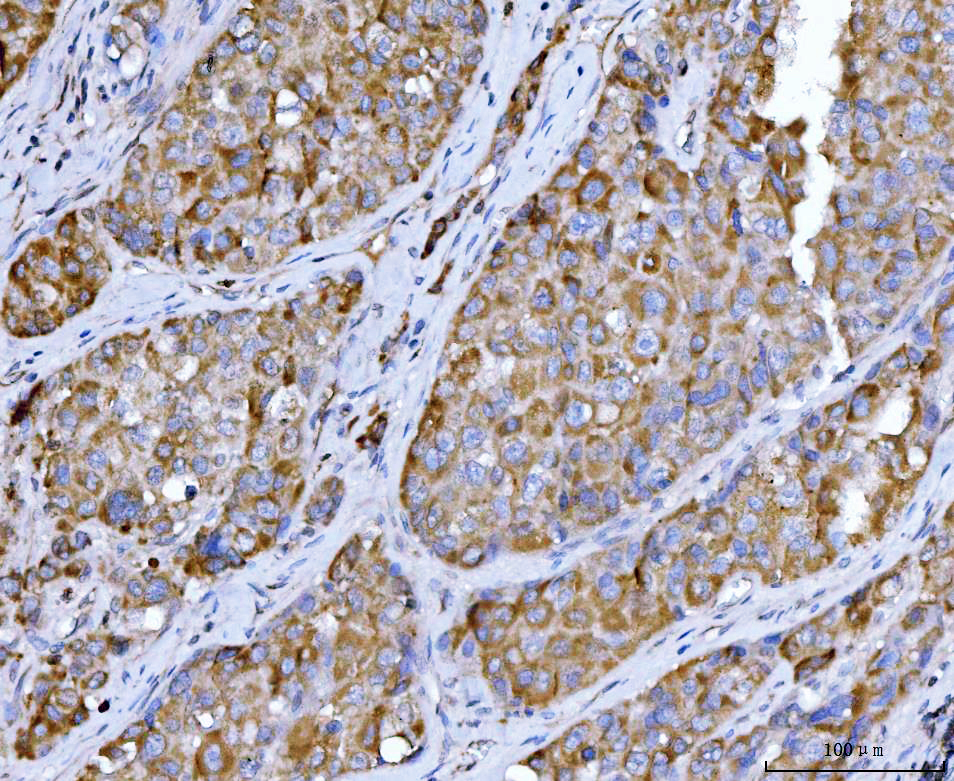

IHC analysis of Beclin 1/BECN1 using anti-Beclin 1/BECN1 antibody (M00327-2).

Beclin 1/BECN1 was detected in a paraffin-embedded section of human breast cancer tissue. The tissue section was incubated with mouse anti-Beclin 1/BECN1 Antibody (M00327-2) at a dilution of 1:200 and developed using HRP Conjugated mouse IgG Super Vision Assay Kit (Catalog # SV0001) with DAB (Catalog # AR1027) as the chromogen.